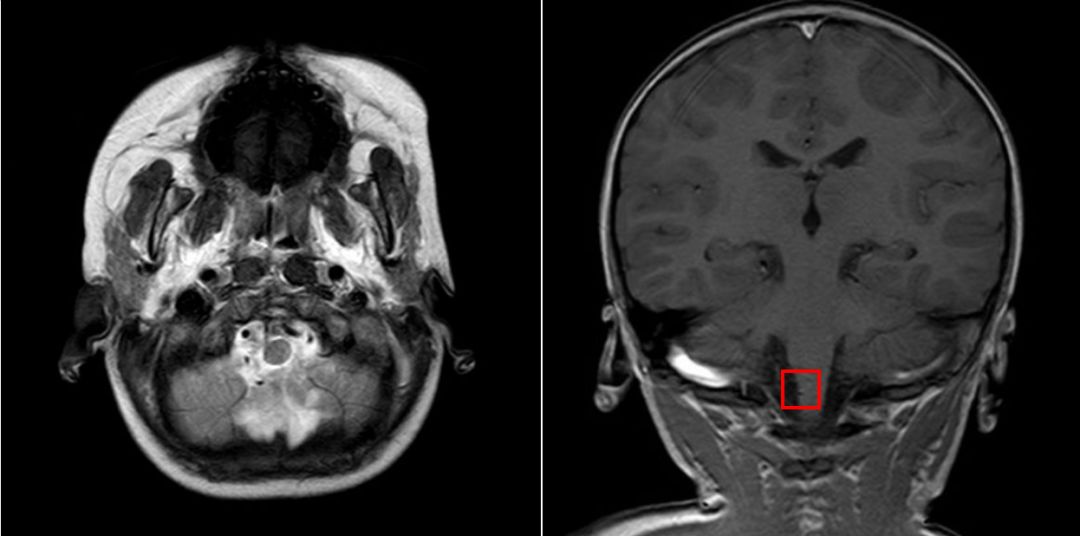

辅检:急诊头颅+颌面部CT示:头颅CT平扫未见明显异常;口腔异物,穿至延髓内,延髓损伤可能(图1)。急诊头颅MRI示:口腔内异物穿至颅内,紧贴延髓右侧,未见伤及颅内大血管,延髓异常信号尚不明显(图2)。急诊血常规:WBC:13.15×10^9/L,N:47.7%,HB:119 g/L,PLT:211×10^9/L,CRP<0.5mg/L。

图2. 头颅MRI:T2水平位可见一低信号的竹签影从患儿口腔内刺入患儿右侧脑干旁,距离右侧小脑后下动脉仅0.5cm;从T1冠状位片中的红色区域内可见右侧脑干有一针孔状低信号区,为竹签刺入处。